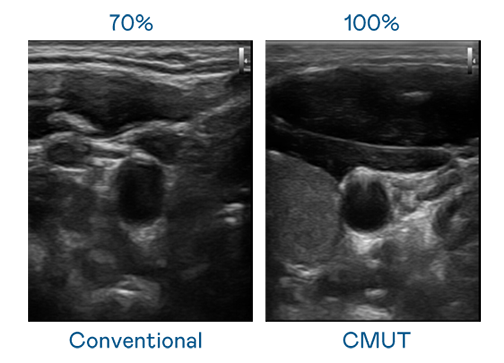

CMUT 技术是一种用电容式微机电元件来产生超音波讯号的技术。与传统 PZT 压电式技术相比,CMUT 频宽增加 30%,更宽频的超音波讯号让影像解析度大幅提升,是实现高影像品质医疗超音波扫描、促进精准医疗发展的关键技术。

大频宽带来超清晰影像

超音波影像的解析度高低,首先取决于探头能发出的讯号频宽。MK体育 CMUT 可提供高清晰的超音波讯号,提供高频宽、高灵敏度、影像纹理细节更高的超音波影像,协助医护人员缩短影像判读时间及利用精准的医疗影像进行诊断。